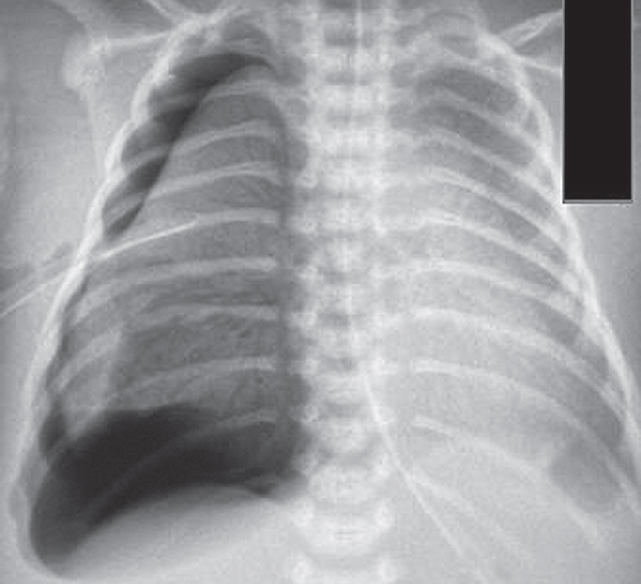

В левый главный бронх повторно введен порактант-альфа. После выполнения манипуляции отмечается клинико-рентгенологическое улучшение (рис. 4) — увеличение SpO2 до 90 %, положительная динамика газового состава крови.

Рис. 4. Рентгенограмма органов грудной клетки новорожденного после повторного монобронхиального введения сурфактанта

Fig. 4. Chest X-ray of newborn after repeated monobronchial administration of surfactant